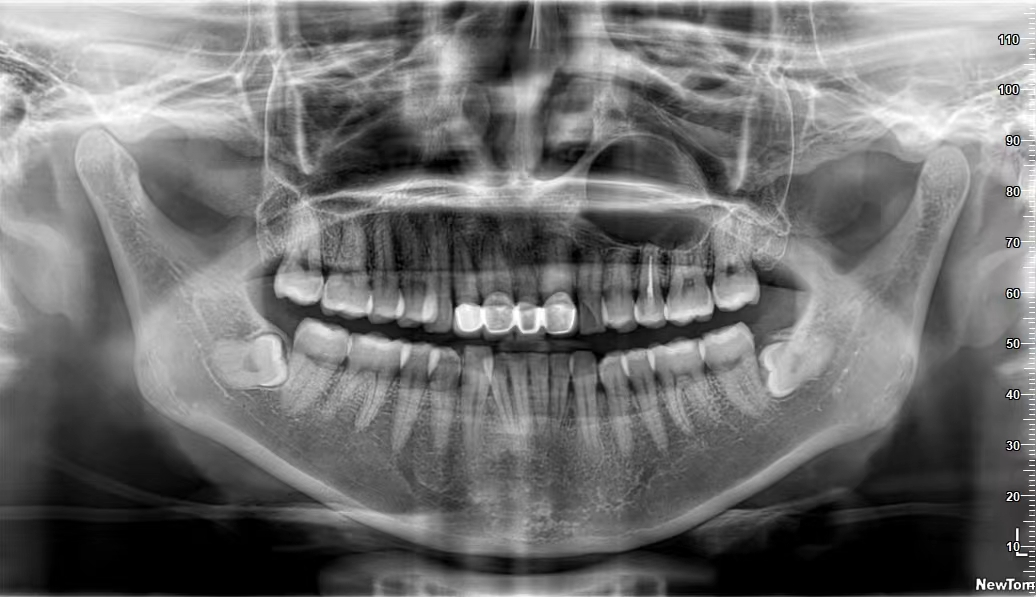

口腔曲面断层篇(全景片)

通过X线球管与胶片匣相对弧形运动,将上下颌骨的结构展示为连续的平面影像。常用于观察恒牙、乳牙龋坏情况;下颌神经管、上颌窦、上下颌骨囊肿,外伤,炎症等情况及其与周围组织的关系。

恒牙期曲面断层片